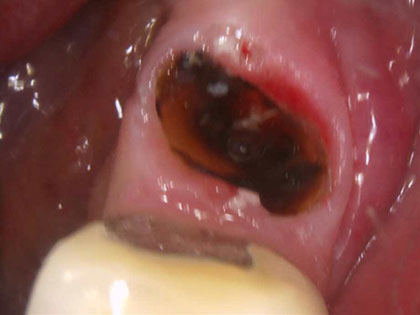

• 治療中の写真がこちら

• インプラント治療中1

• 左下5が定期的に腫れる。ブリッジを除去してみると歯根破折をしており、残すのが難しい状態。